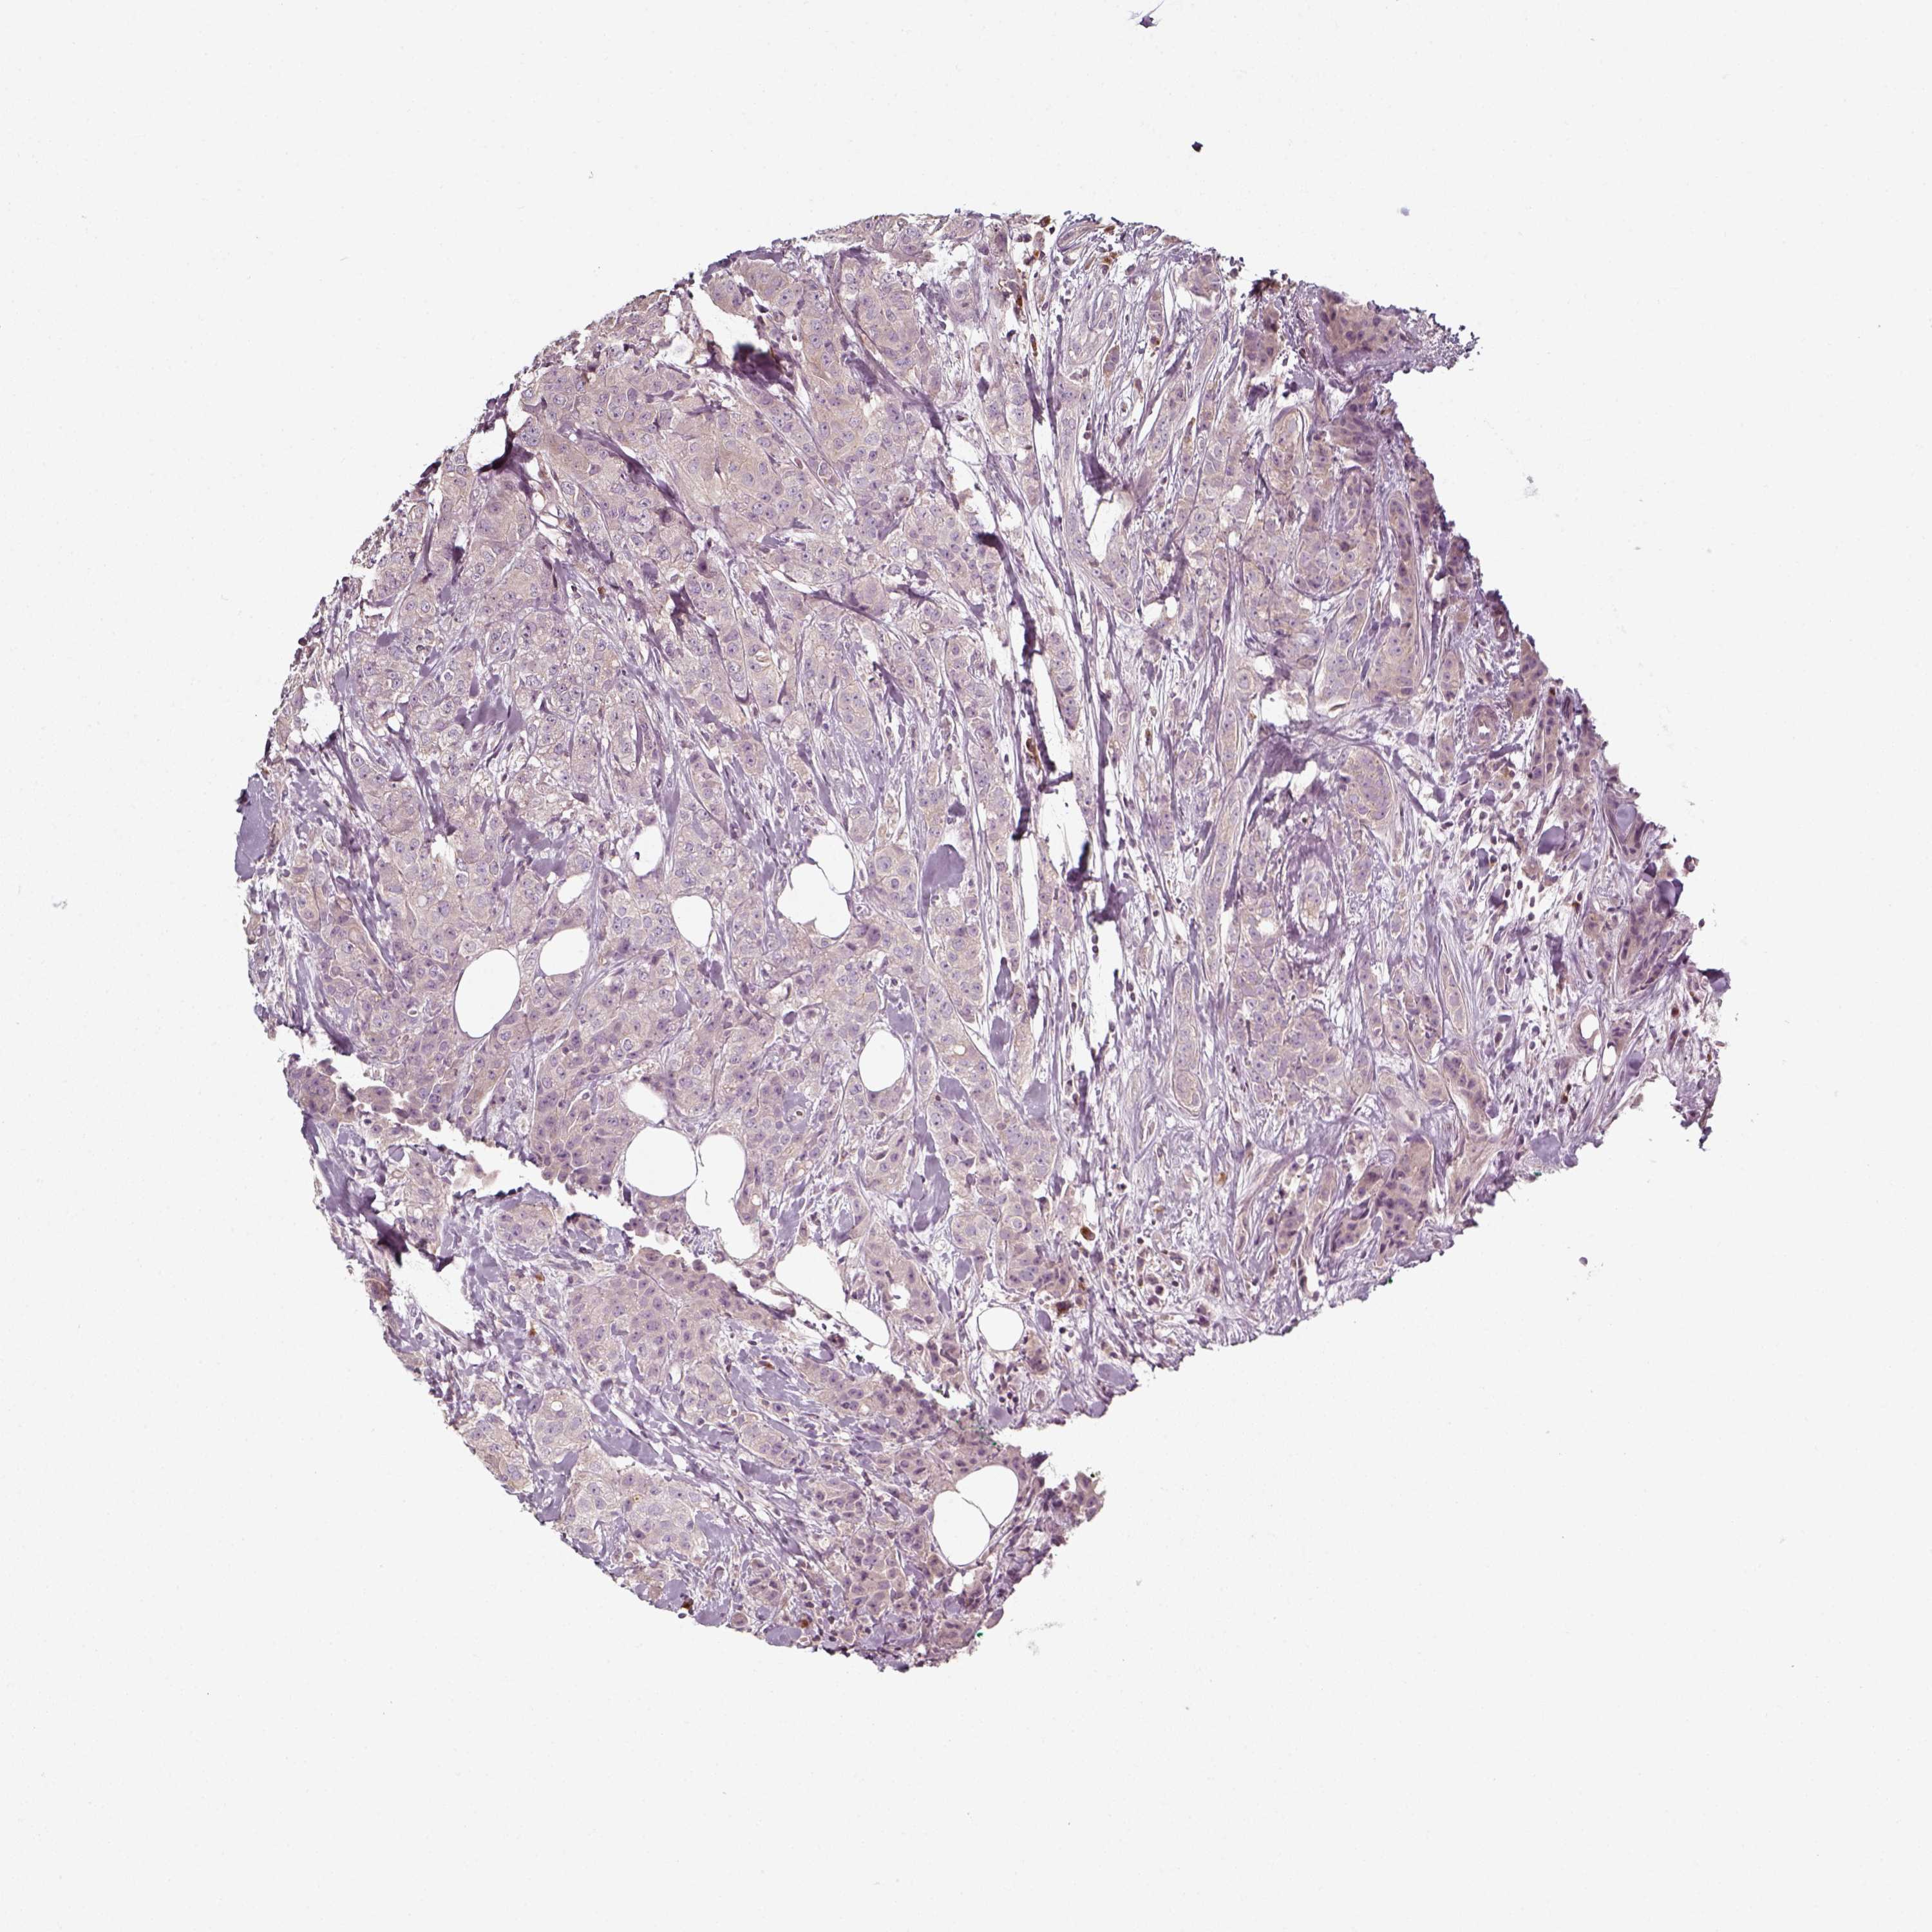

CANCER BREAST CANCER Show tissue menu

BRCA TCGA BRCA VALIDATION PROTEIN EXPRESSION